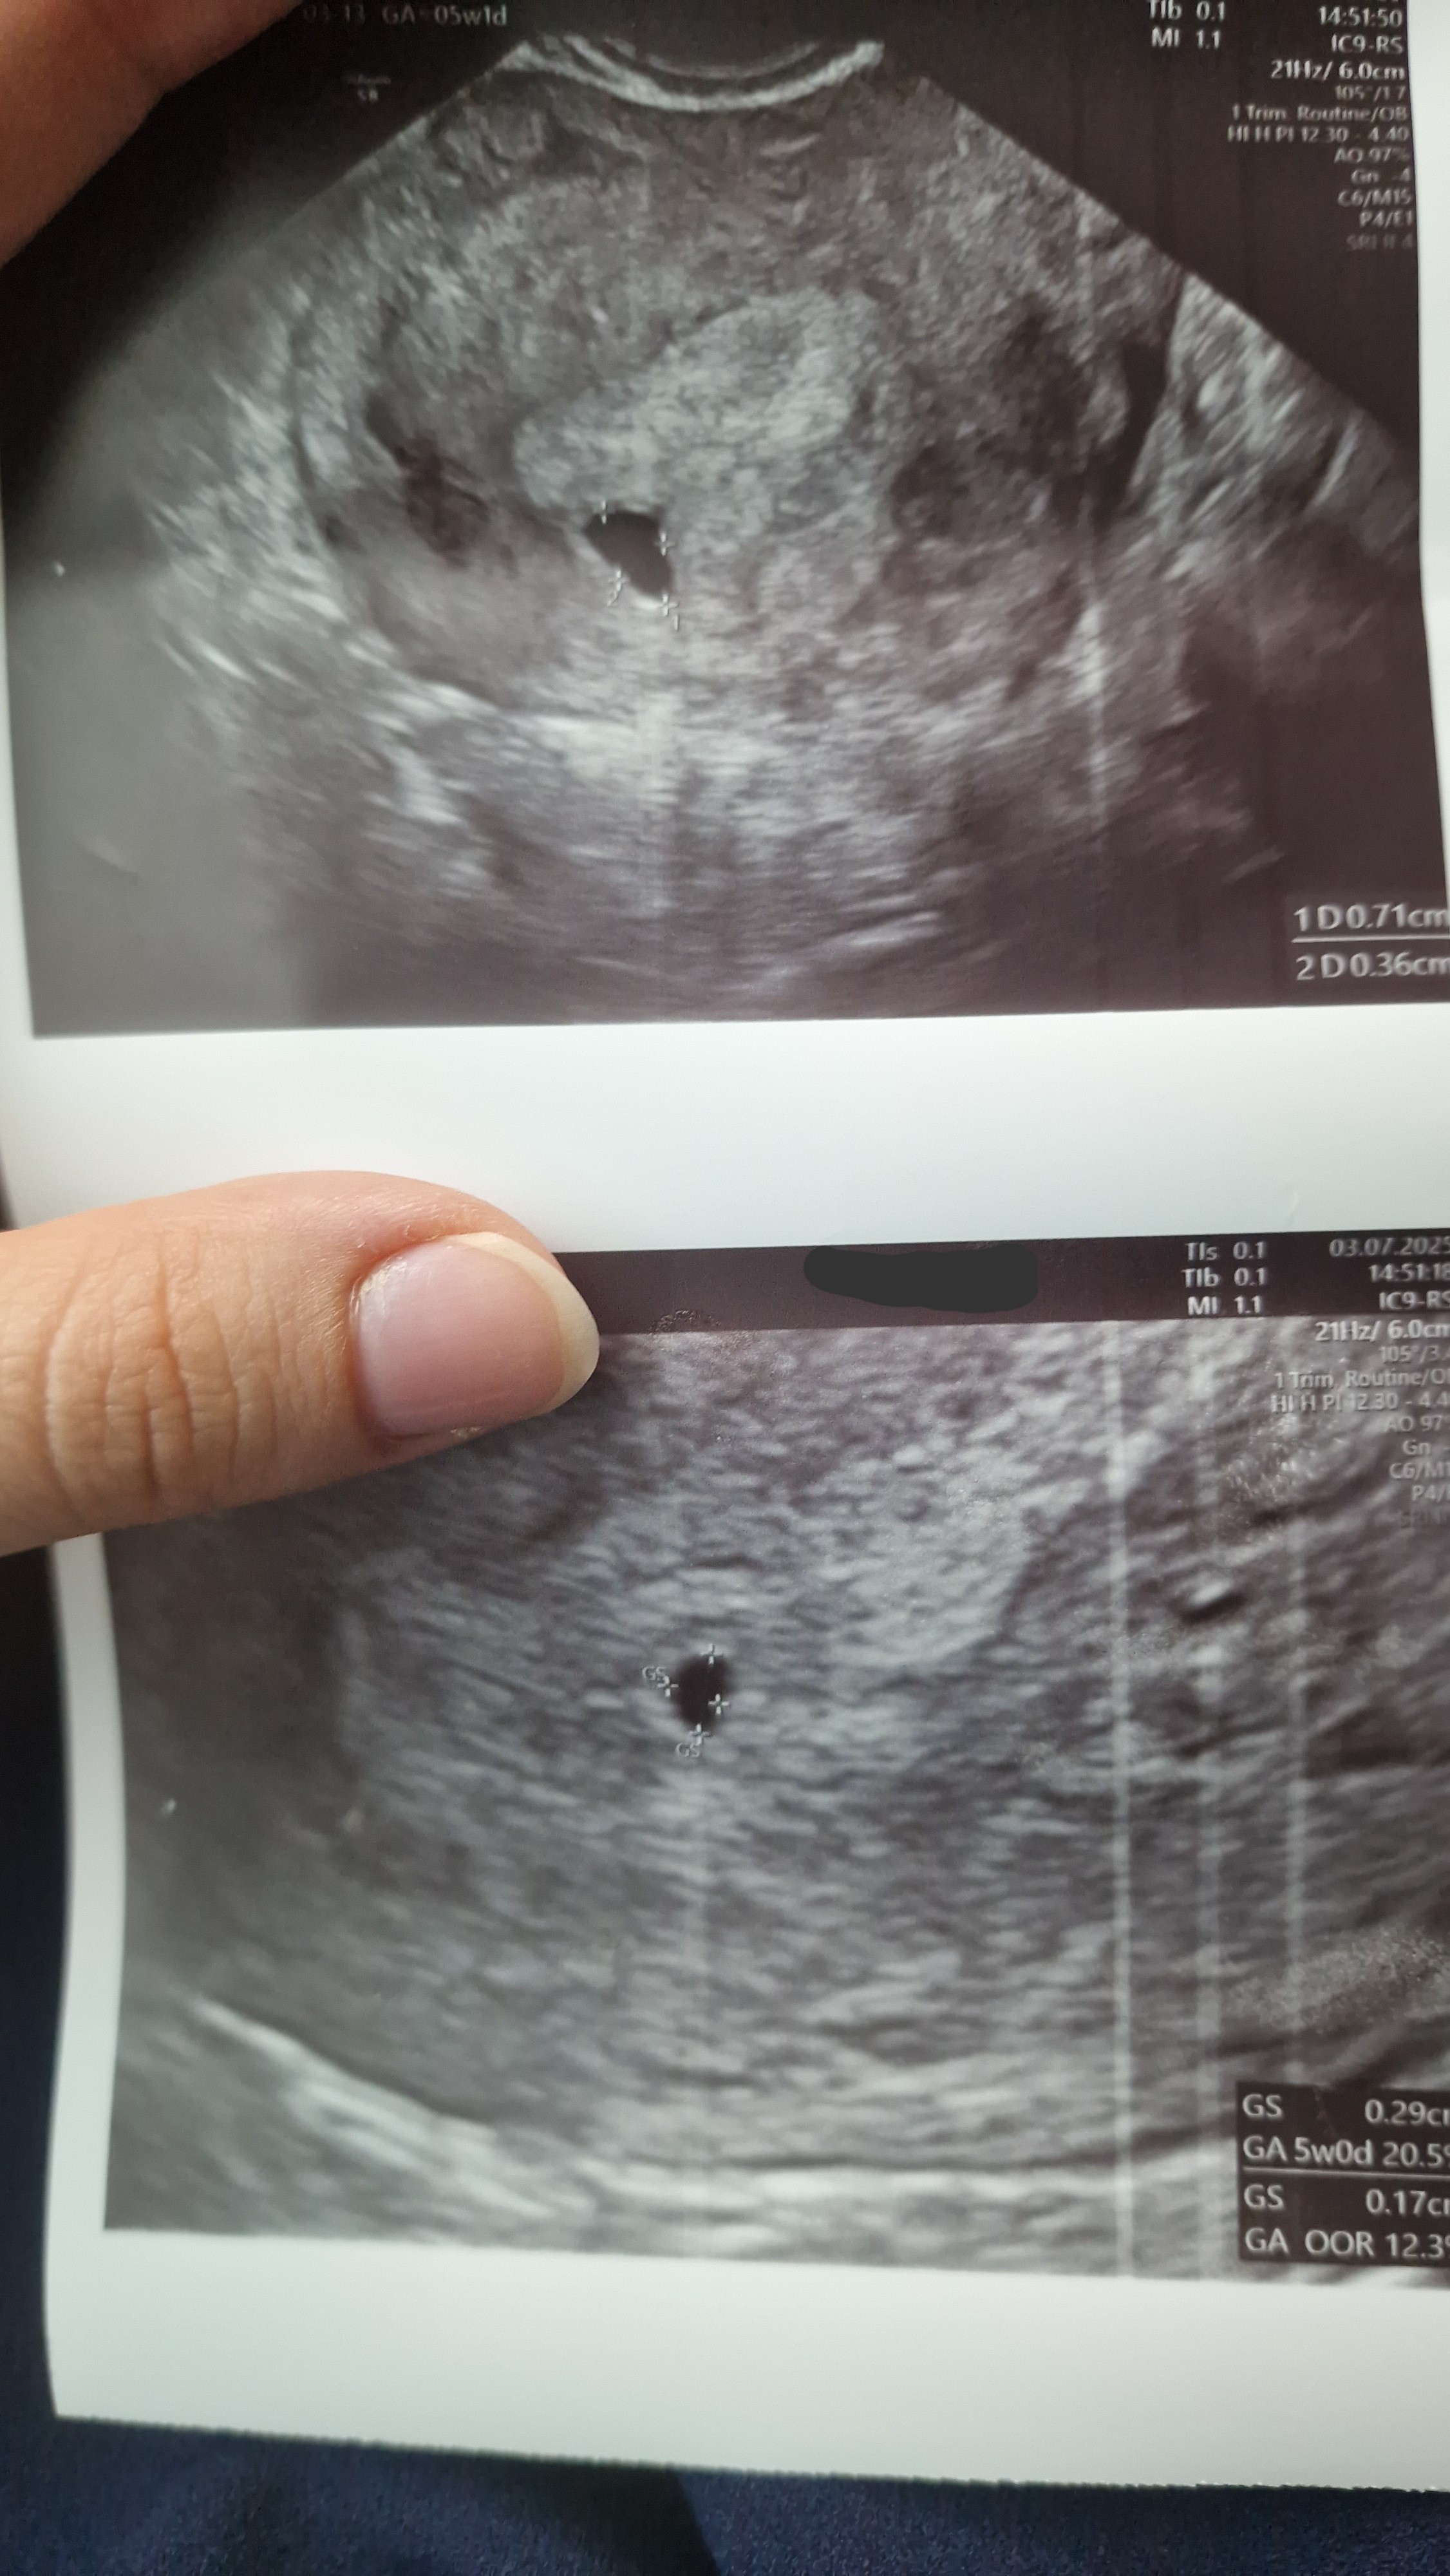

Ja dziś byłam na wizycie, bo potrzebowałam recepty. Okazuje się, że są dwa pęcherzyki ale lekarz mówił, że jeden to chyba pseudopęcherzyk

• 20250703_153122.jpg

20250703_153122.jpg

1,5 MB · Wyświetleń: 195